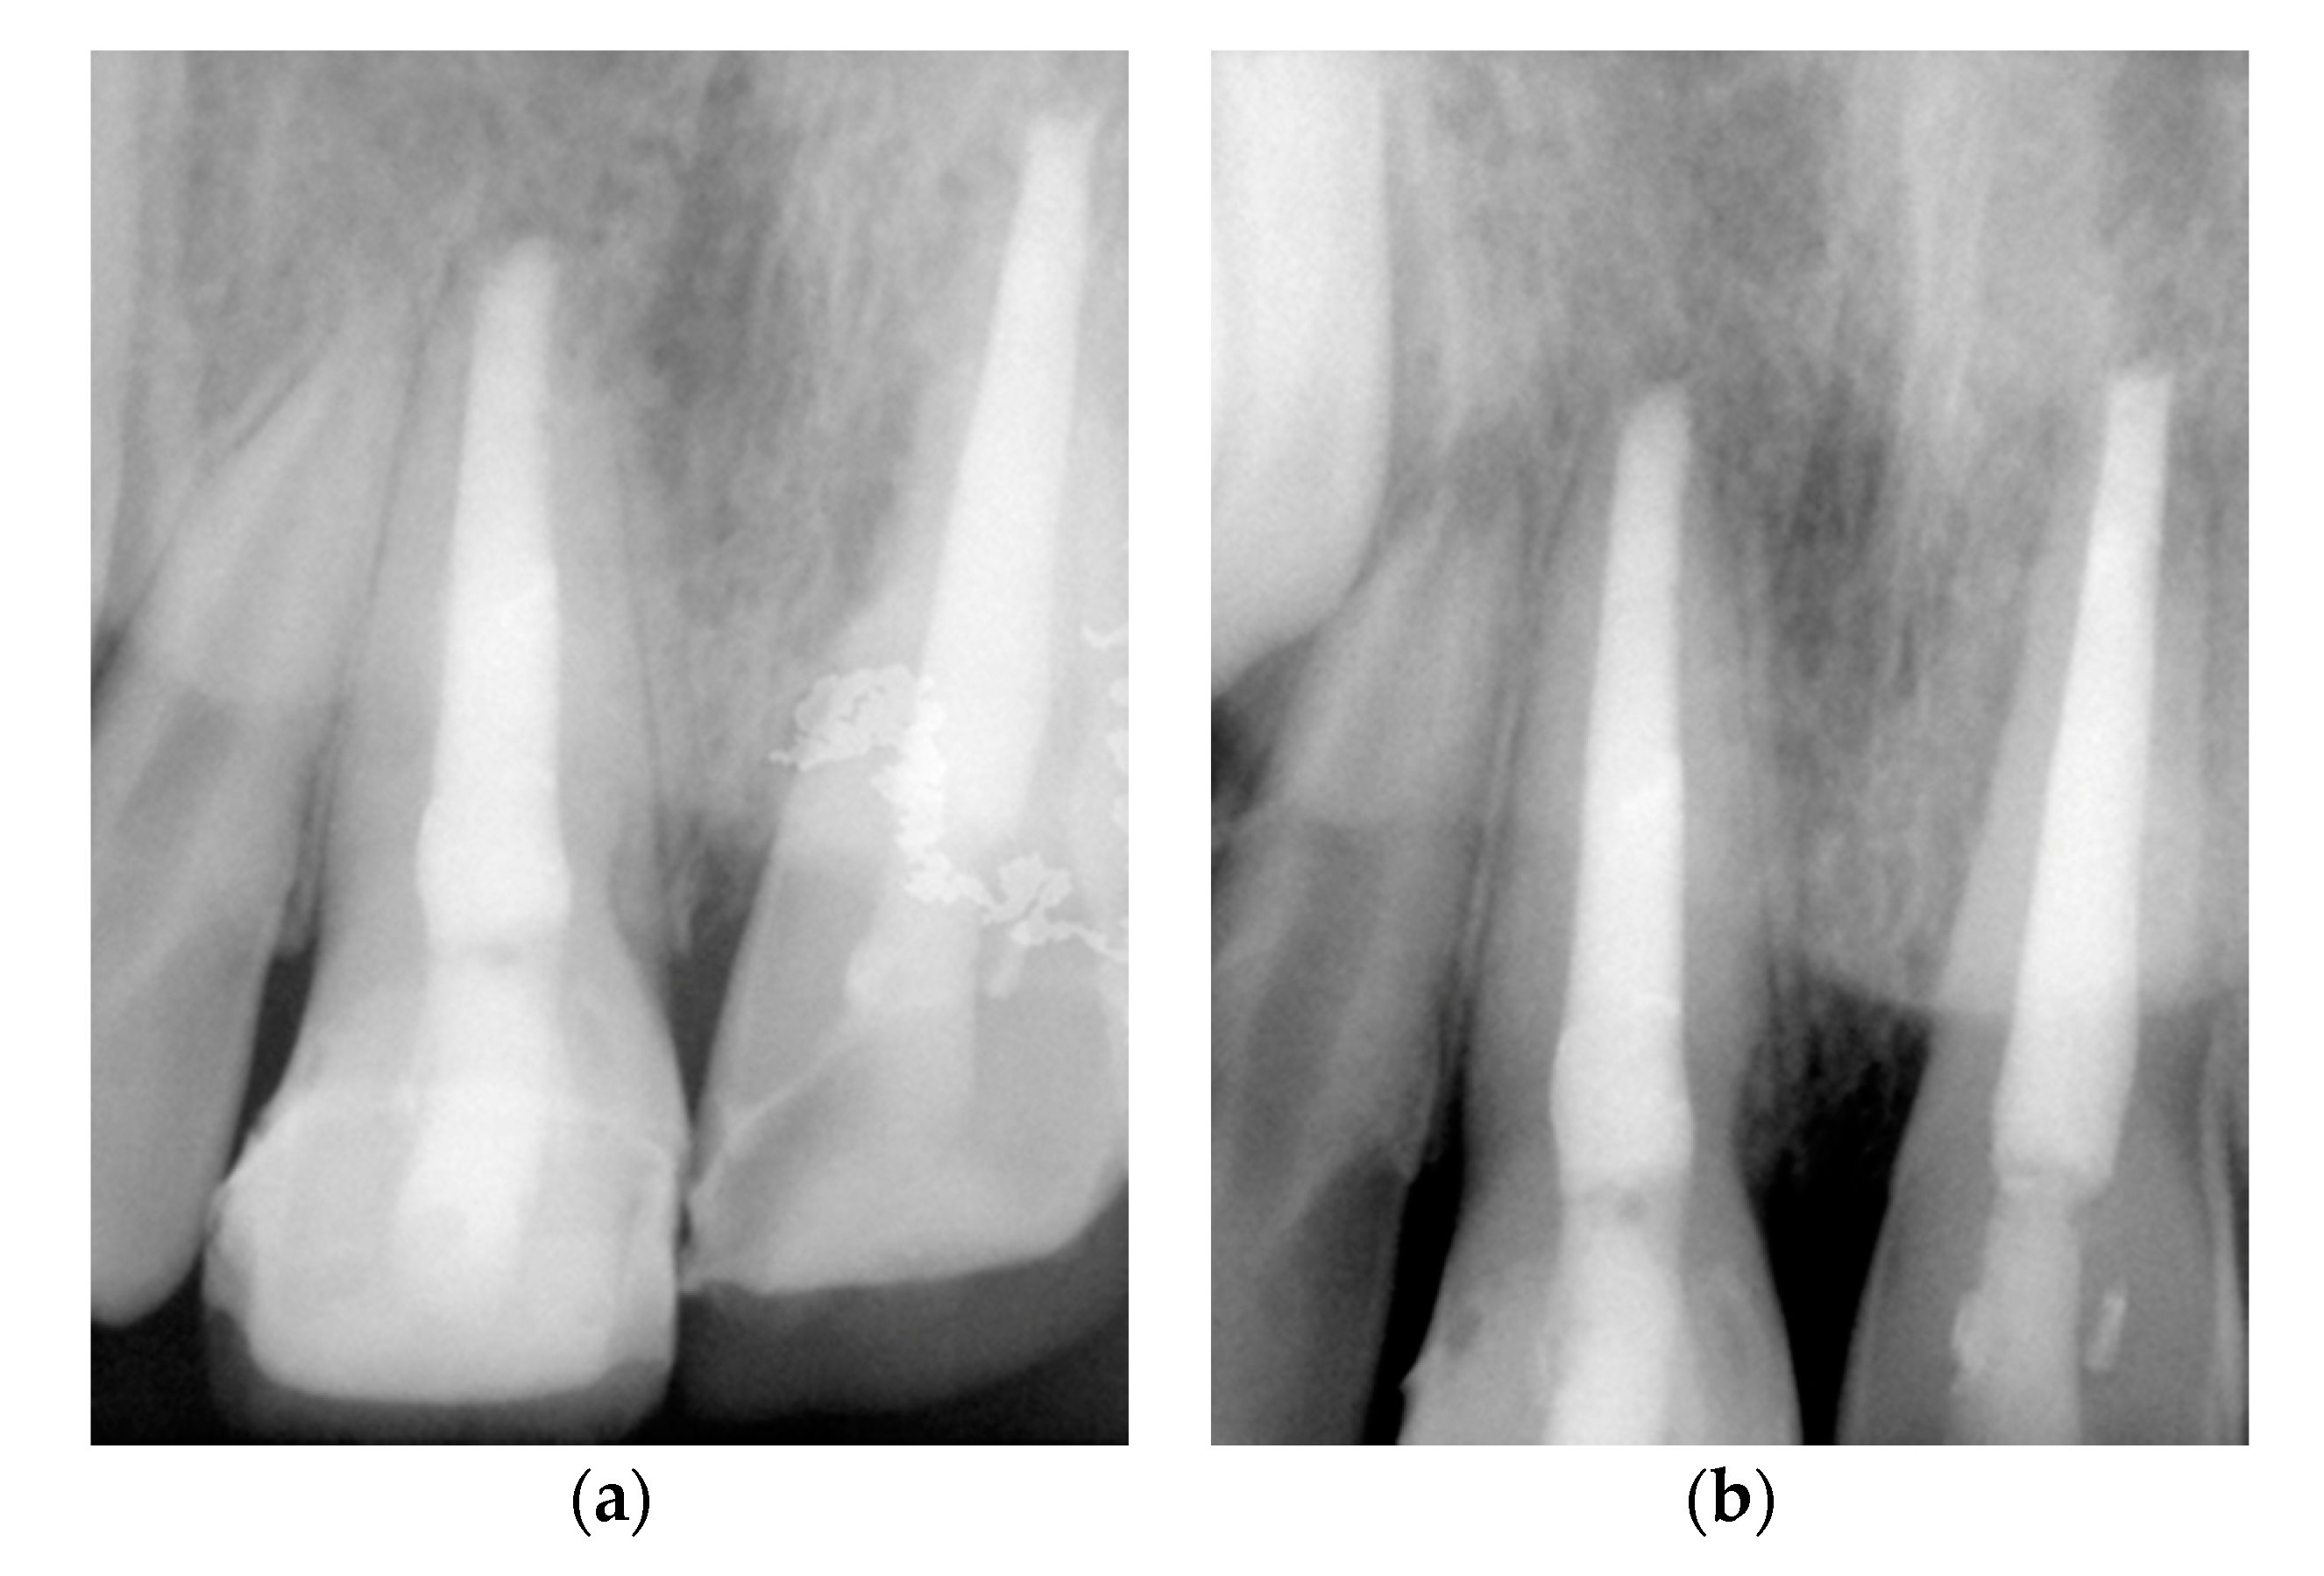

2. Case Presentation